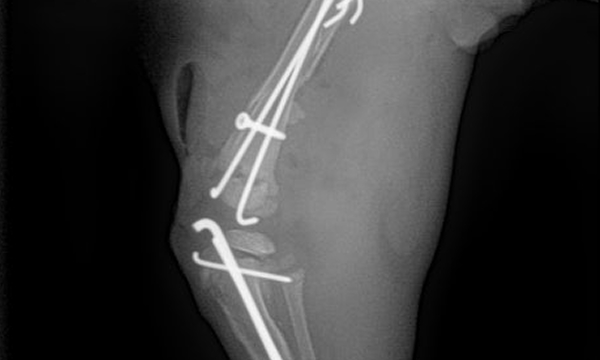

수술케이스 ③ 배*강아지 - 대퇴골 분쇄골절

수술케이스 3 before BEFORE

수술케이스 3 after AFTER